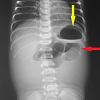

Jejunal atresia with ileojejunal knotting: An unusual presentation

Jejunoileal atresia, Bowel knottingAbstract